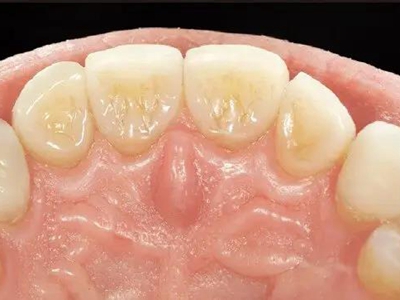

牙齿

坑

酸蚀症牙齿内侧有凹坑发黄图

出现酸蚀症时,牙齿内侧会在腐蚀下形成凹陷的坑,大小不一,坑处牙齿表面发黄,形似茶渍。该病的发生可能与胃液反流,内源性酸性物质腐蚀牙面导致。